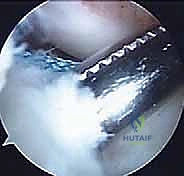

شكل 5: رؤية بالمنظار الجراحي بتقنية 4K عالية الدقة لمفصل الركبة من الداخل، مما يتيح للأستاذ الدكتور محمد هطيف رؤية أوضح للتشريح الدقيق وإجراء الجراحة بأقل قدر من التدخل الغازي.

- المنظار الجراحي: يتم إدخال كاميرا المنظار 4K عبر ثقبين صغيرين جداً في الركبة. يتم أولاً فحص المفصل بالكامل، ومعالجة أي تمزقات في الغضاريف الهلالية (خياطة الغضروف أو تهذيبه).